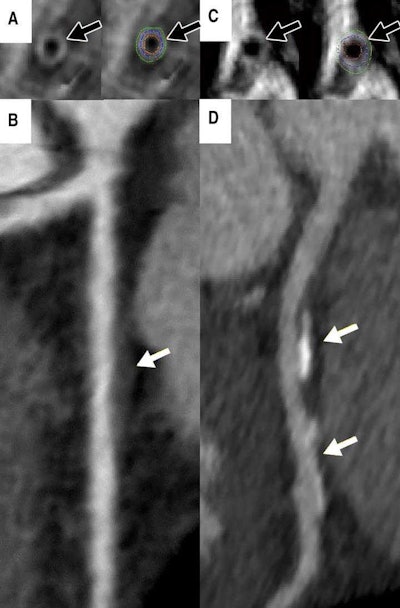

A: Cardiac MRI in a 46-year-old asymptomatic woman shows measured vessel wall thickness of 1.3 mm (black arrows). B: CT angiography shows noncalcified plaque (white arrow) in the proximal left anterior descending coronary artery. C: Cardiac MRI in a 44-year-old asymptomatic woman shows thicker coronary vessel wall (black arrows). D: CT angiography shows coronary artery disease (white arrows). Courtesy of the Radiological Society of North America.

A: Cardiac MRI in a 46-year-old asymptomatic woman shows measured vessel wall thickness of 1.3 mm (black arrows). B: CT angiography shows noncalcified plaque (white arrow) in the proximal left anterior descending coronary artery. C: Cardiac MRI in a 44-year-old asymptomatic woman shows thicker coronary vessel wall (black arrows). D: CT angiography shows coronary artery disease (white arrows). Courtesy of the Radiological Society of North America.The fact that MRI of vessel wall thickness proved to be a strong independent factor of heart disease in young women is a promising study finding that could positively influence patient care, the team noted.